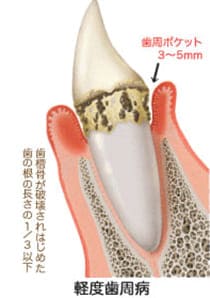

軽度歯周炎

軽度の歯周炎は歯茎が少し赤みを帯び腫れた状態になります。

軽度歯周炎の場合の目安は歯周ポケットが3~5mm程度と言われています。この段階での治療法は、プラークや歯垢をスケーリングなどで取り除き、正しいブラッシングを毎日することです。 -